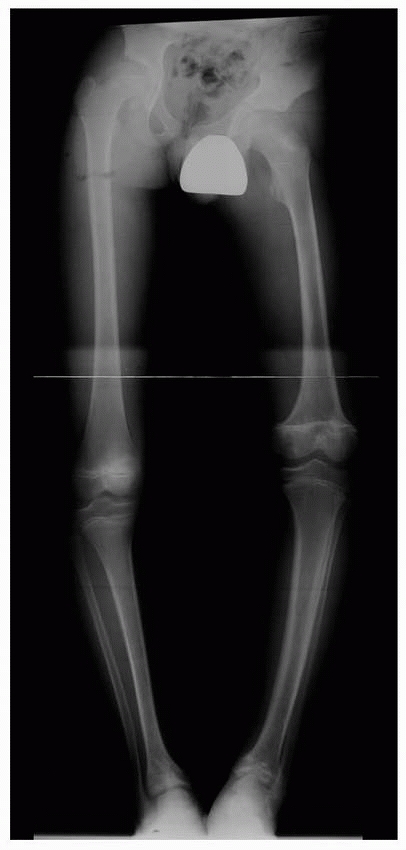

| Figure 5-6 Standing anteroposterior lower extremity radiograph of a 12-year-old boy with multifocal physeal disturbance from purpura fulminans associated with meningococcemia. Radiograph abnormalities are present in the left proximal femur; both distal femoral epiphyses, including partial arrest of the left distal femoral physis; and both distal tibial epiphyses. The patient also has digital amputations and extensive soft-tissue scarring resulting from this septic event. |